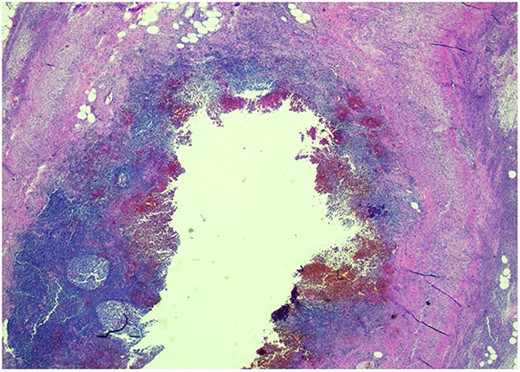

Pathology resulted on post-operative day three showing an inflamed appendix, 1.4 cm in diameter, with an exudative-filled lumen. On microscopic stains, there was evidence of acute appendicitis with frequent scattered unicellular organisms within areas of ulcerated appendiceal mucosa and submucosa (Figs 6 and 7). These cellular forms have round cell membranes, single prominent round eosinophilic nuclei and foamy cytoplasm (Fig. 5). Occasional forms show evidence of erythrophagocytosis (Fig. 3). Forms were also highlighted by trichrome and PAS special stains (block A1) and were negative for CD68 (a marker of macrophages; block A1) (Figs 2–4). These morphologic features are most consistent with E. histolytica, which is a pathogenic parasite in the lower GI tract, and likely the causative agent for acute appendicitis in this case.

H&E 200X—unicellular parasites within submucosal tissue with inflammation.